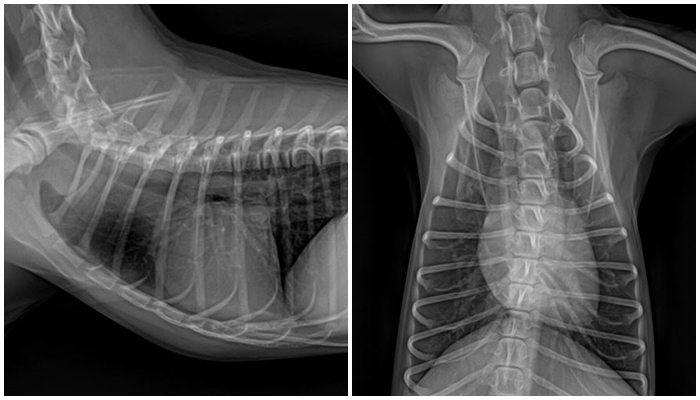

이에 따라 마취 전 검사를 진행했고, 혈액 검사 및 흉부 방사선 검사에서 특이 소견 없이 양호한 상태로 확인되어 안전하게 수술을 준비할 수 있었습니다.

마취 전 흉부 방사선 검사 사진 / 출처: 라온동물메디컬센터